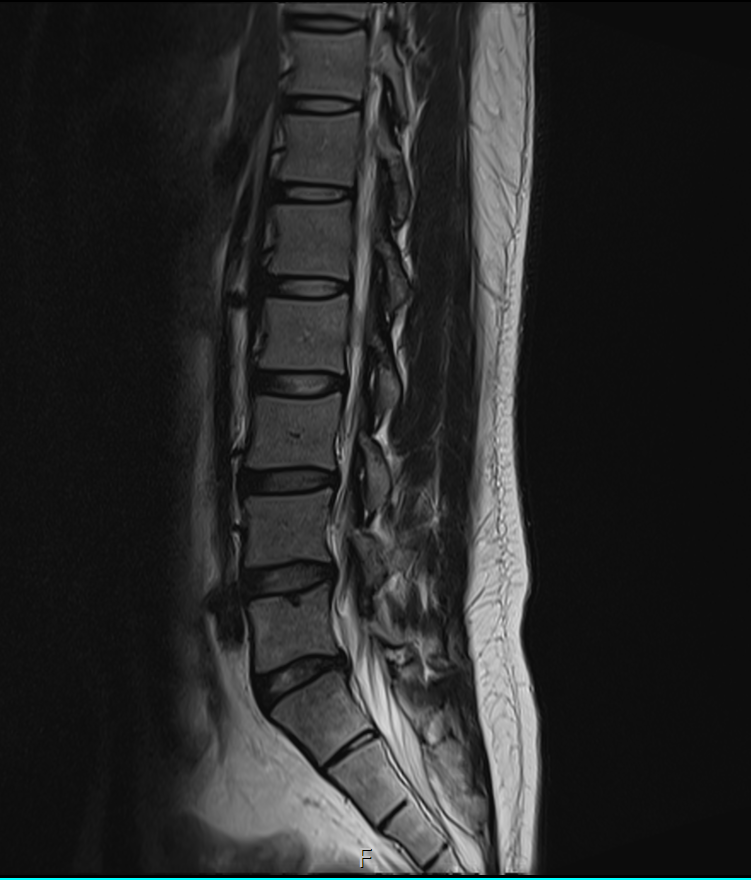

1년전에 허리가 안좋아서 MRI를 찍었는데 저번주에 경미한 교통사고가 났습니다.

그 후 다리에 저림증상이 있기 시작했고 피가 안통하는 느낌이 들기 시작했습니다.

경미한 교통사고가 다리저림에 원인일 수 있을까요? MRI판독 부탁드립니다 ㅠㅠ

1년전

• 1번 째 사진

1년 전 사진에 비해 허리디스크 상황이 악화된 것으로 생각됩니다. 다리저림은 이로 인한 증상으로 생각됩니다.

그러나, 말씀하신 내용과 검사결과만으로는 교통사고와의 연관성에 대해 단정지어 말하기는 어렵습니다. 증상이 점차 악화되어 발생한 것인지, 교통사고에 의해 갑자기 악화된 것인지에 대한 판단이 추가로 필요하겠습니다.